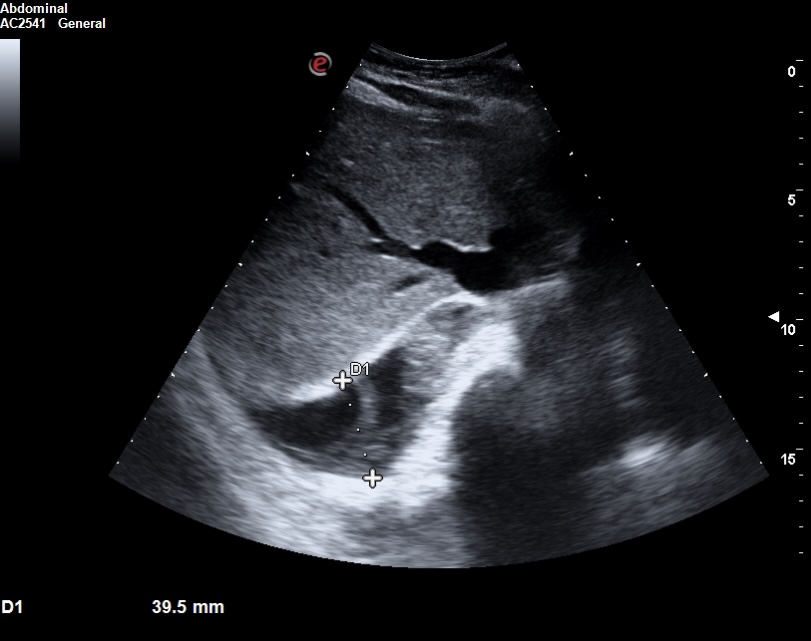

La ecocardioscopia mostró ventrículo izquierdo no dilatado con función sistólica conservada, sin hipertrofia del septo interventricular ni valvulopatías. Aurículas izquierda y cavidades derechas de tamaño normal. TAPSE normal. Se evidenció un derrame pericárdico moderado sin signos de taponamiento cardíaco. Calibre de vena cava inferior normal con colapsabilidad mayor del 50%. Hallazgo de derrame pleural derecho moderado.

La ecografía clínica desempeñó un papel fundamental en la evaluación inicial del paciente, permitiendo una detección rápida y precisa de hallazgos que guiaron la toma de decisiones clínicas. La ecocardioscopia realizada reveló un derrame pericárdico moderado, sin signos de taponamiento cardíaco y un derrame pleural derecho significativo. Estos hallazgos fueron esenciales para descartar la presencia de un cuadro obstructivo que pudiera haber requerido una intervención inmediata. Además, la ecografía permitió valorar el estado hemodinámico de la paciente de forma no invasiva, asegurando que el derrame pericárdico no comprometiera la función cardíaca. En la radiografía de tórax se objetiva una masa mediastínica. La capacidad de detectar y cuantificar de forma precisa tanto el derrame pleural como el pericárdico sin necesidad de esperar a pruebas más complejas, permitió que la paciente fuera ingresada de manera adecuada para un estudio exhaustivo y sin demoras innecesarias.